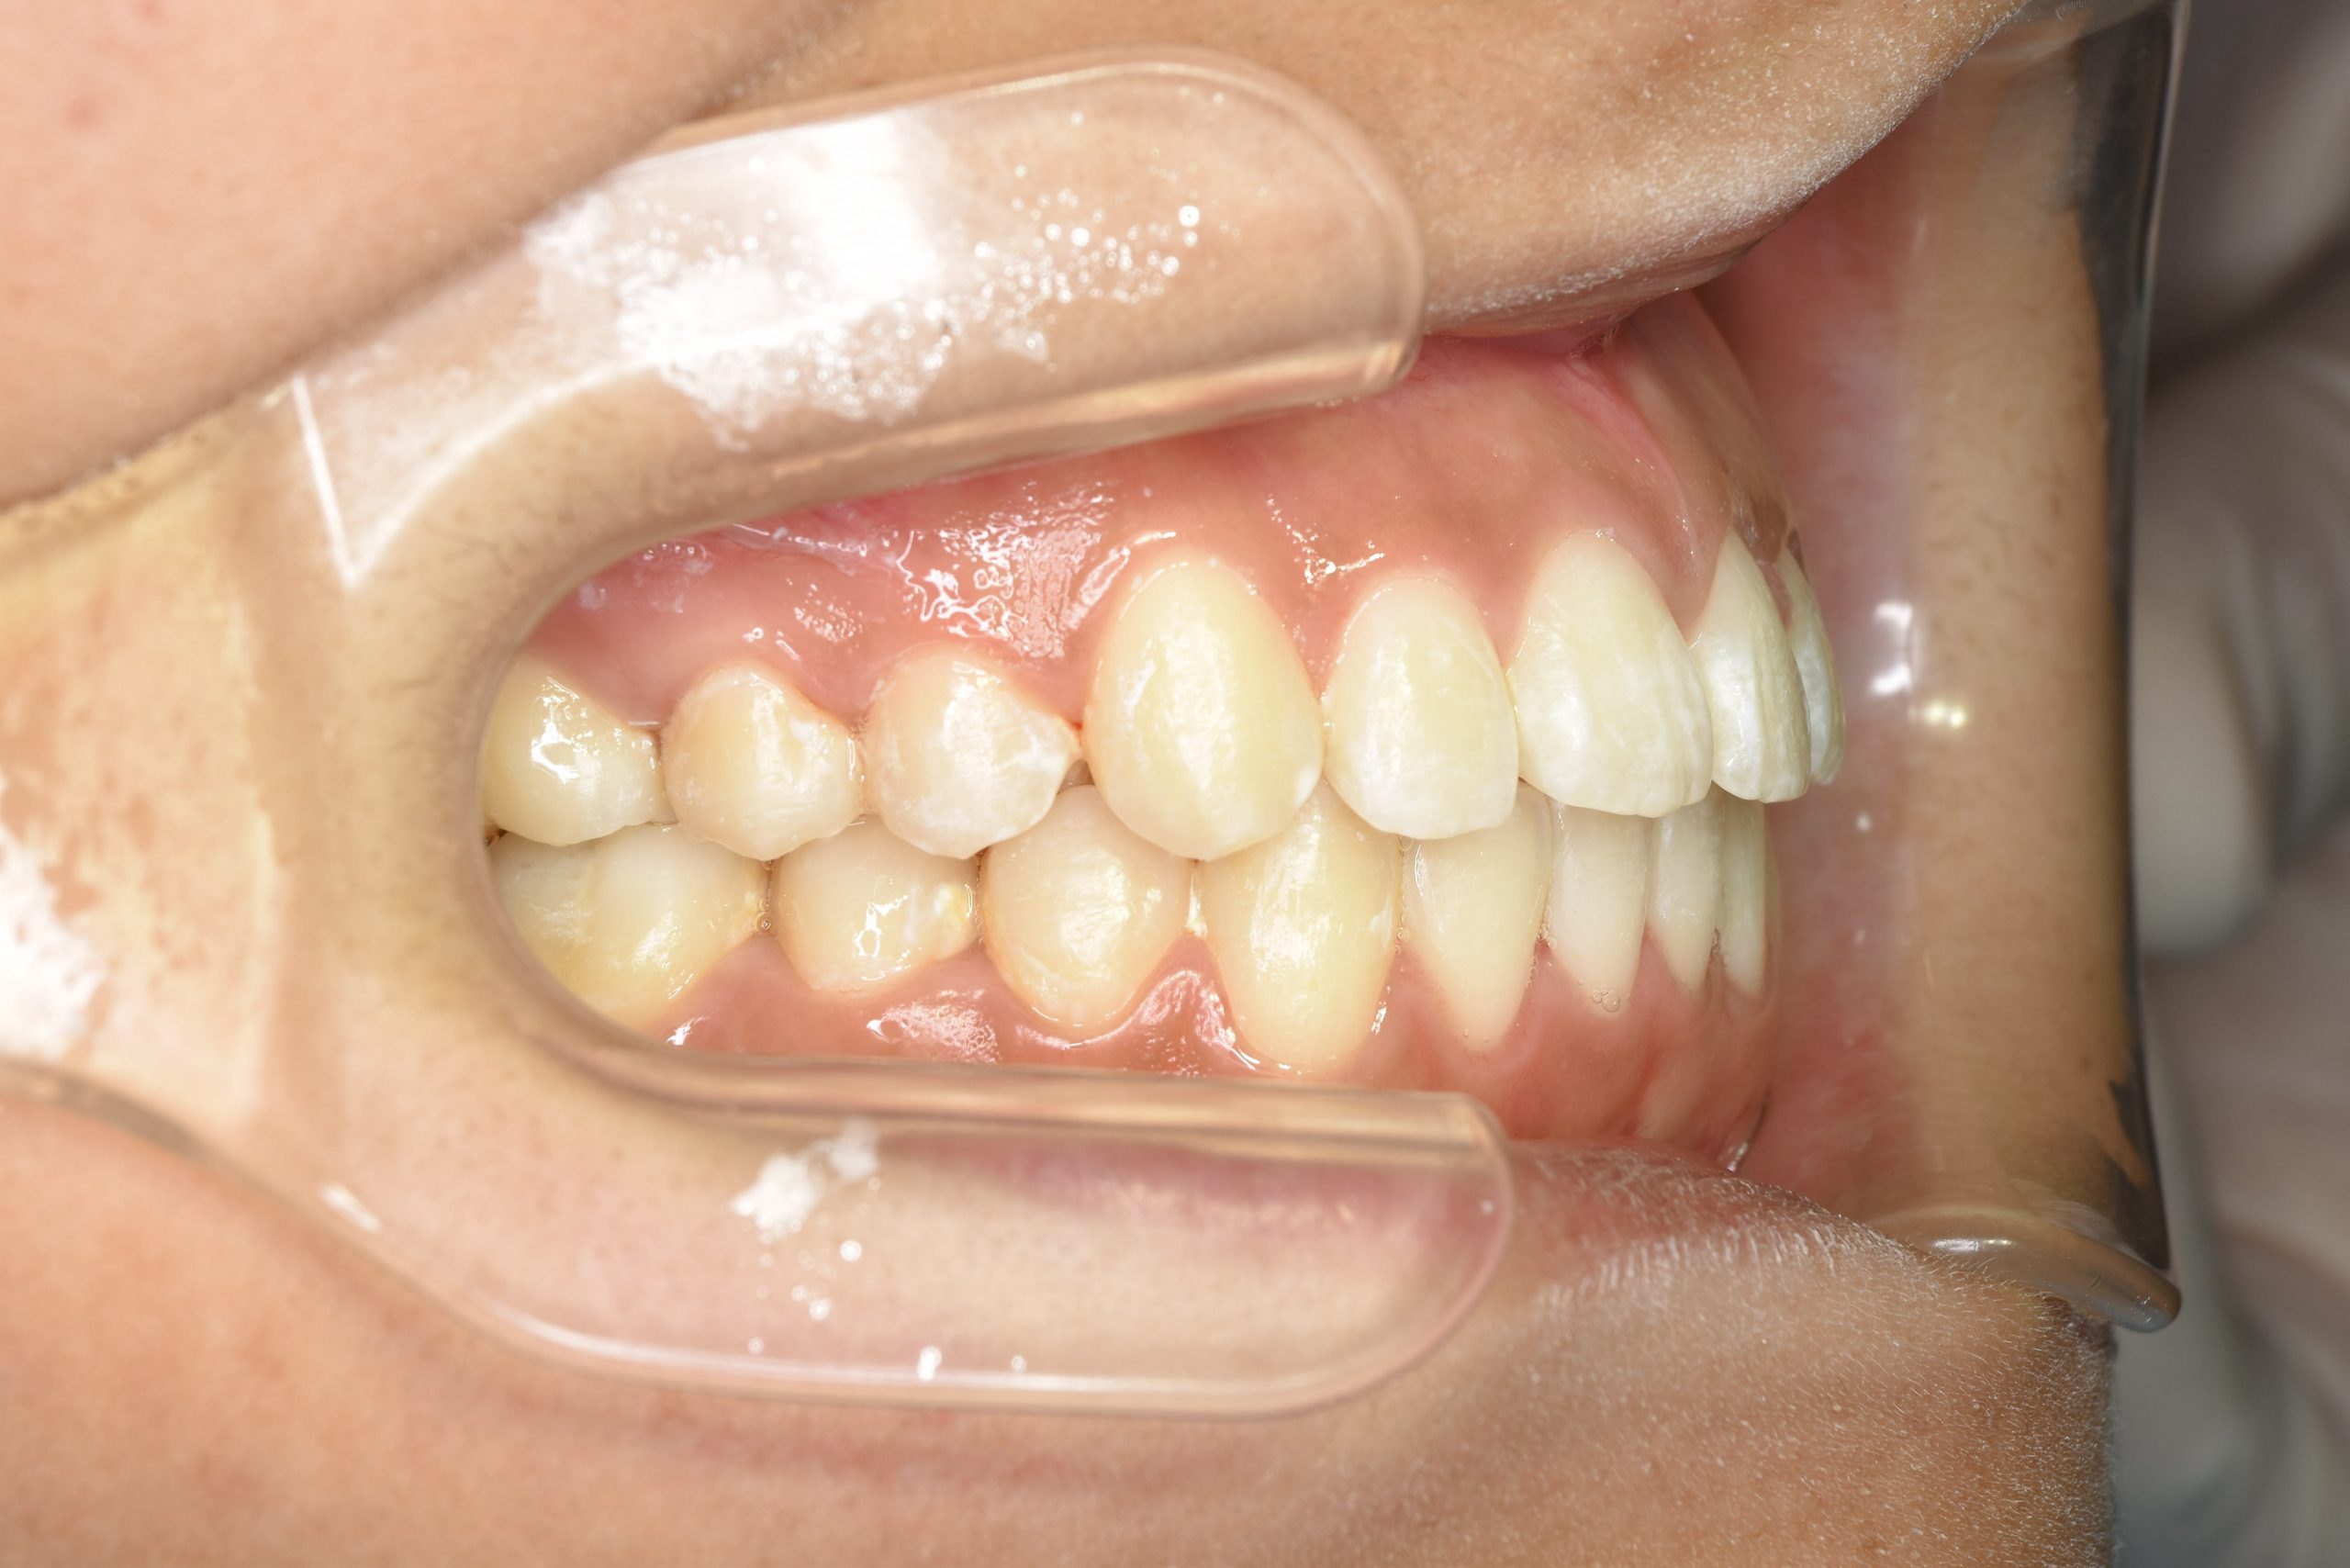

アフター

全顎ワイヤー矯正 症例_839

主訴 前歯の歯並び

施術内容 成人矯正1期治療

治癒期間 1年2か月間

費用 954,800円(税込)

リスク・副作用 違和感、不快感、痛み